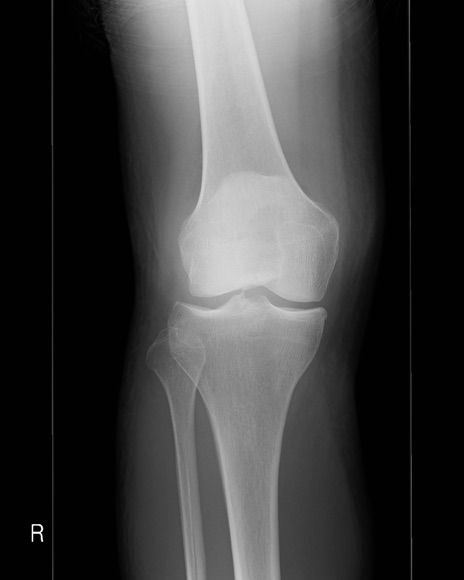

症例28 右膝関節レントゲン(正面像)

【症例】60歳代女性

【主訴】右膝痛

【現病歴】本日椅子より転落し受傷。右膝痛及び歩行困難となり来院。

【身体所見】右膝腫脹++、右足関節の運動は良好、感覚障害なし。

異常所見と診断は?

右膝関節レントゲン